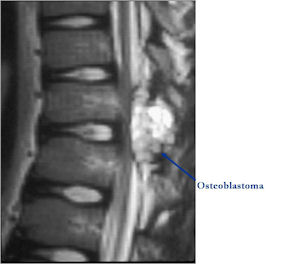

- Spine (40% of cases; usually posterior elements)

MRI:

- Also useful in determining extent

- There is often extensive edema around the tumor in the surrounding bone and soft tissues that can lead to a misdiagnosis of a malignant tumor.

Osteoblastoma